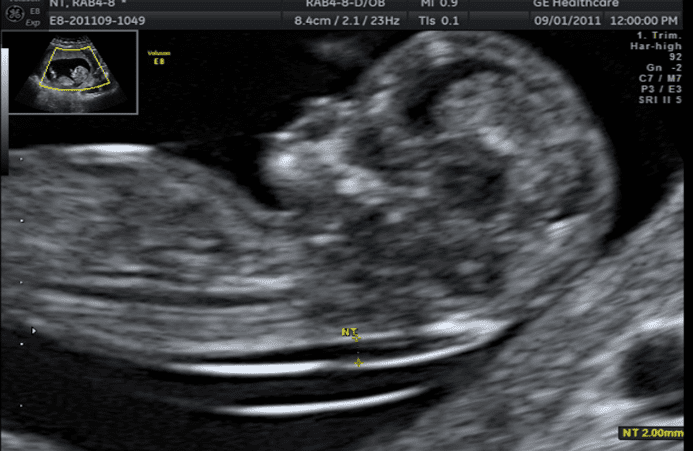

태아 후경부투명대(NT)검사

태아의 기형을 진단하는 기본 초음파검사이며 예약이 필요합니다. 임신 11-13주 사이에 태아의 후경부투명대 두께를 측정하여 태아의 기형아 위험도, ‘다운증후군’ 및 심장기형 등을 알아내는 검사입니다.